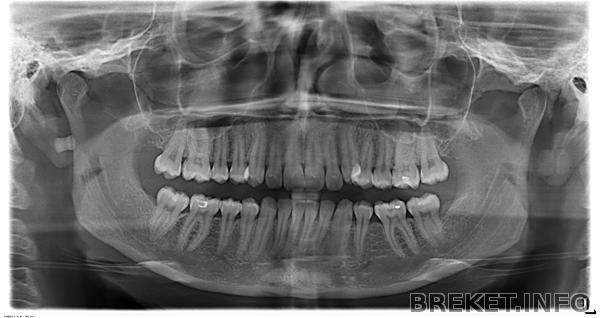

Целью № 1 является теоретический анализ существующих зубных форм (кривота)